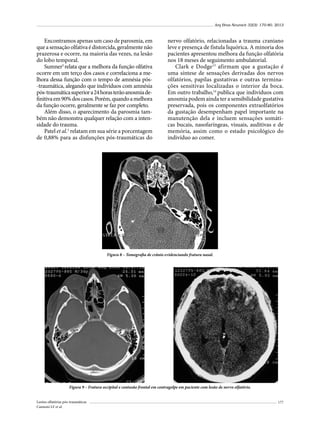

crianças foram diagnosticadas com FEC. Todos nossos

casos sofreram TCE antes dos primeiros três anos de

vida; quatro crianças apresentaram história de queda de

altura e uma criança foi vítima de acidente de trânsito.

A prevalência de FEC nos pacientes com fraturas de

crânio em nosso estudo foi de 0,4%, e na literatura varia

entre 0,03% e 1,6% (Tabela 2).19,24,26,28-32

Em relação ao sexo, em uma revisão pessoal feita de

15 diferentes séries, incluindo nosso estudo, somando

um total de 255 casos de FEC, apenas 11 séries apresentaram dados relacionado ao sexo dos pacientes.